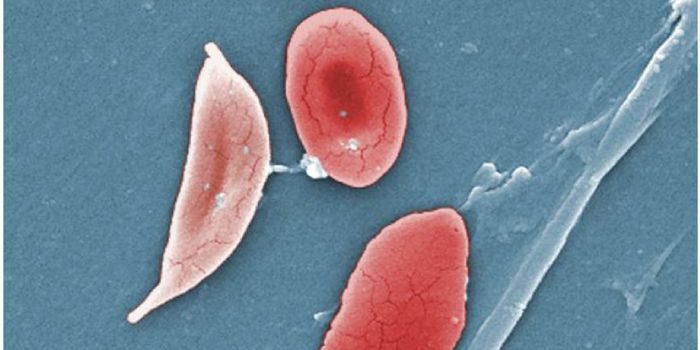

JUL 25, 2017Clinical & Molecular DXFor the first time in almost two decades, patients with sickle cell disease will have access to a new drug thanks to a r ...